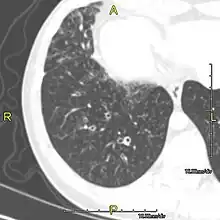

Around 80% of people with primary ciliary dyskinesia experience respiratory problems beginning within a day of birth. Many have a collapsed lobe of the lung and blood oxygen low enough to require treatment with supplemental oxygen.[1] Within the first few months of life, most develop a chronic mucus-producing cough and runny nose.[1] The main consequence of impaired ciliary function is reduced or absent mucus clearance from the lungs, and susceptibility to chronic recurrent respiratory infections, including sinusitis, bronchitis, pneumonia, and otitis media. Progressive damage to the respiratory system is common, including progressive bronchiectasis beginning in early childhood, and sinus disease (sometimes becoming severe in adults). However, diagnosis is often missed early in life despite the characteristic signs and symptoms.[2] In males, immotility of sperm can lead to infertility, although conception remains possible through the use of in vitro fertilization, there also are reported cases where sperm were able to move.[8] Trials have also shown that there is a marked reduction in fertility in females with Kartagener's syndrome due to dysfunction of the oviductal cilia.[9]

Many affected individuals experience hearing loss and show symptoms of otitis media which demonstrates variable responsiveness to the insertion of myringotomy tubes or grommets. Some patients have a poor sense of smell, which is believed to accompany high mucus production in the sinuses (although others report normal – or even acute – sensitivity to smell and taste). Clinical progression of the disease is variable, with lung transplantation required in severe cases. Susceptibility to infections can be drastically reduced by an early diagnosis. Treatment with various chest physiotherapy techniques has been observed to reduce the incidence of lung infection and to slow the progression of bronchiectasis dramatically. Aggressive treatment of sinus disease beginning at an early age is believed to slow long-term sinus damage (although this has not yet been adequately documented). Aggressive measures to enhance clearance of mucus, prevent respiratory infections, and treat bacterial superinfections have been observed to slow lung-disease progression. The predicted incidence is 1 in approximately 7500.[10]